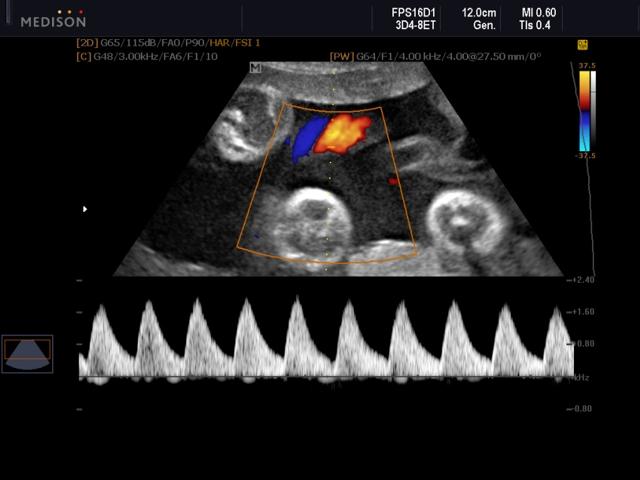

Плод, кровообращение, энергетический допплер

Сосуды пуповины, триплексный режим